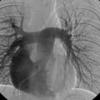

PA angio

Fig 1